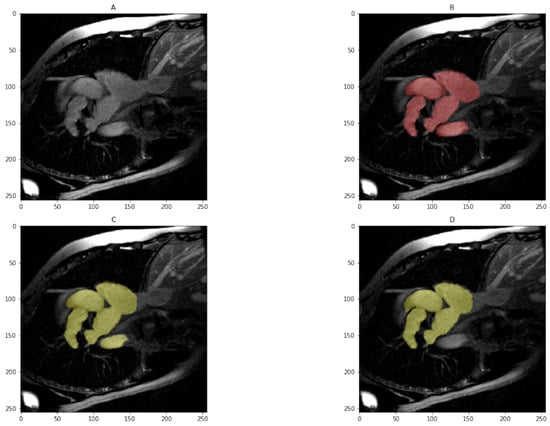

Both the imATFIB and ACDC datasets are split 80/20 into a training and validation set. Evaluation is done at the original resolution of the images. The mean Dice is computed by averaging over the Dice of each volume. For the imATFIB dataset, we measure the Dice on two classes only: heart vs background. An example set of images from the imATFIB dataset is presented in Figure 2. Evaluation scripts provided by the ACDC challenge were used to compute metrics.

Figure 2.

Sample results from the imATFIB validation set (Red—ground truth, Yellow—model prediction). (A) Input image, (B) Label mask, (C) All Ensemble model (), (D) U-net model ().